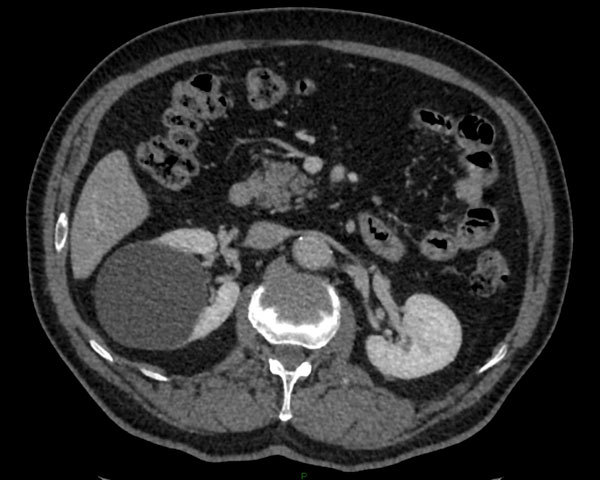

Diagnostic?

Petite tumeur rénale droite trouvée de manière fortuite sur un scanner